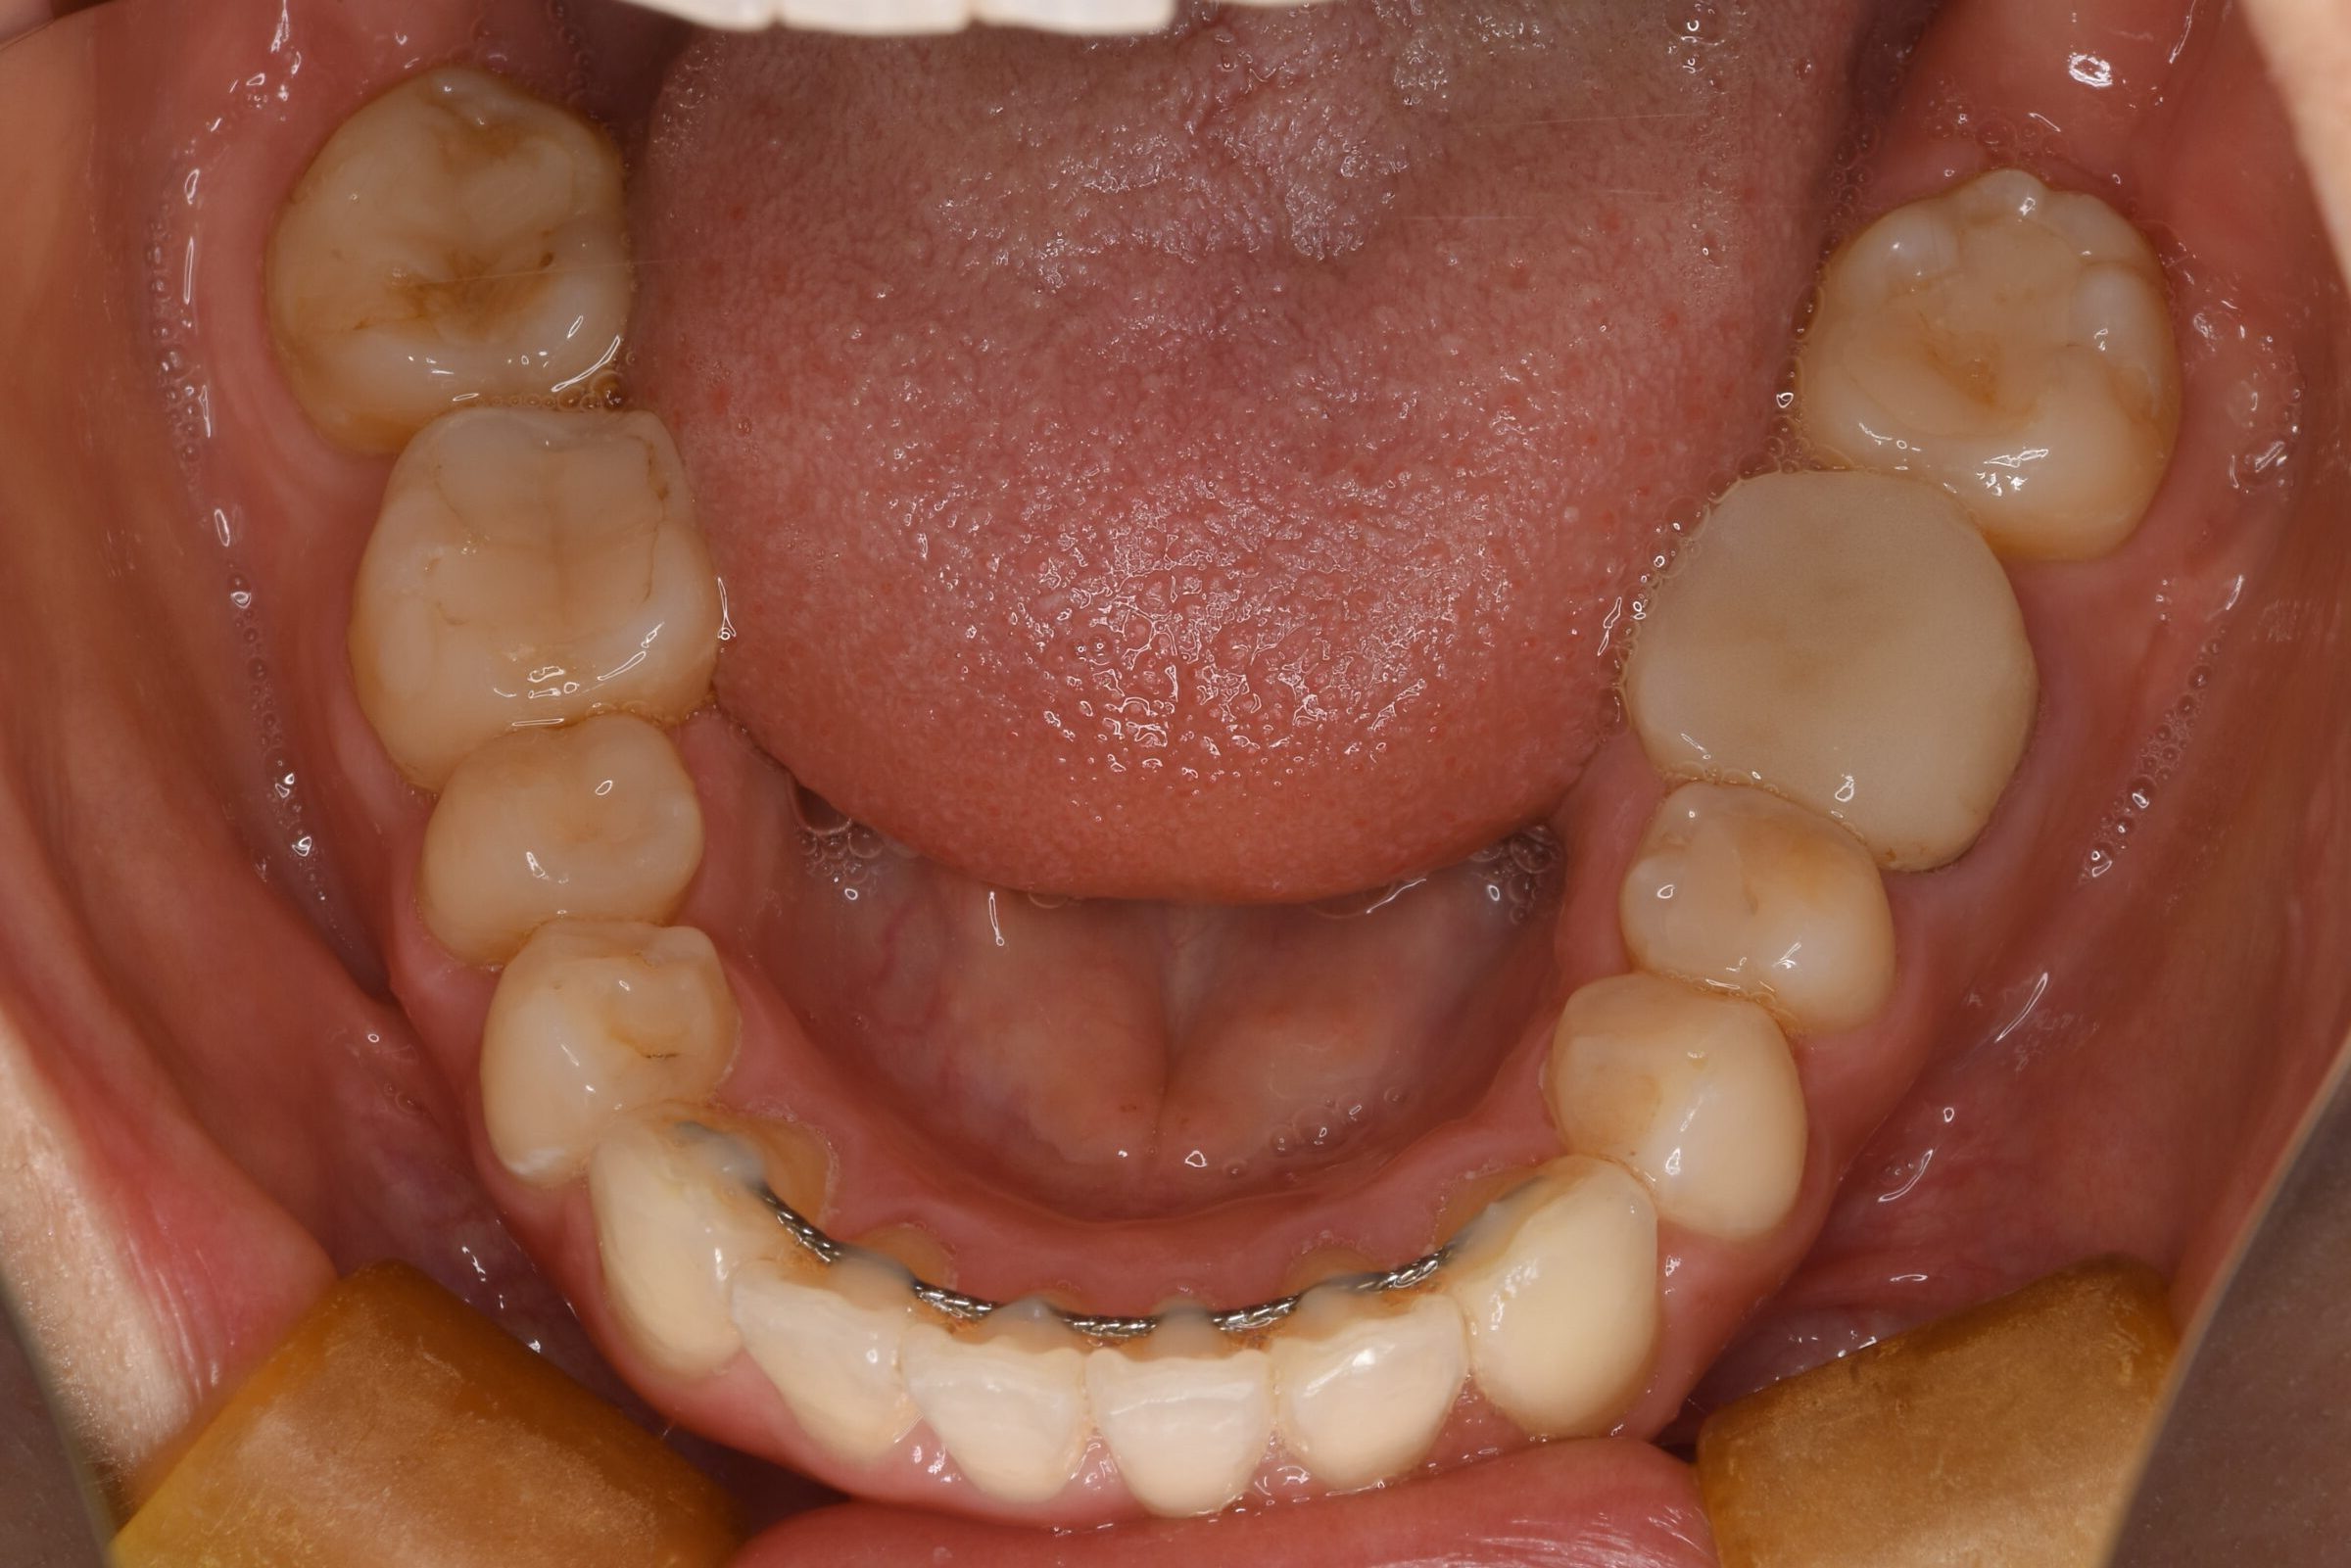

上下の変化はこちら!

凄くきれいに整ったと思いませんか??

歯科治療には散々悩まされてきましたが、根本からしっかり治療したことでようやく繰り返す治療から抜け出すことが出来たと思います。

これから銀歯や昔の詰め物を取り換えていくので、さらに美しい口腔内になると思います!!

ここから先は院長によるセラミック治療で、さらに完璧な口腔内を目指していきます!